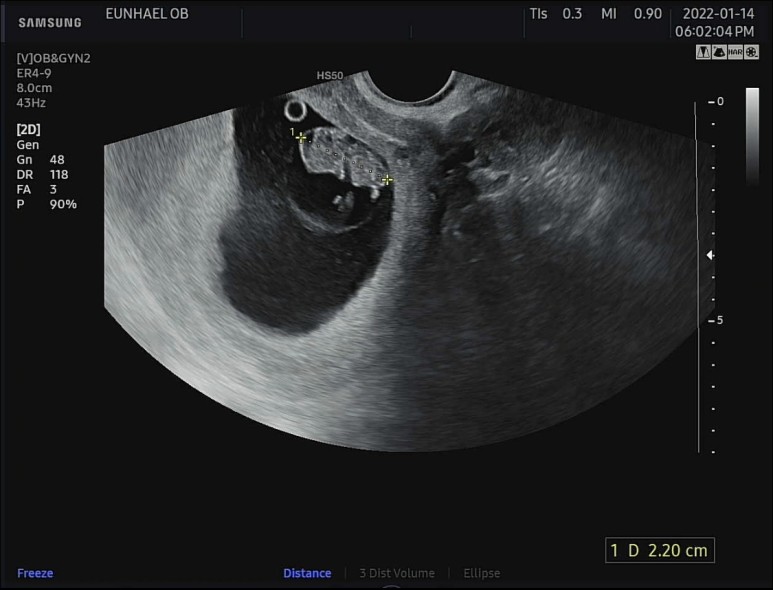

헤헷, 짜잔~!

귀여운 젤리곰 보고 가세요~~

무려 2등신의 젤리곰이 되었다 '^'!!

머리 위에 동그란 난황 도시락도 아주 야무지게 잘 가지고 있는 우리 젤리곰♡

키는 0.8cm에서 무려 1.2cm나 자란 2.2cm!

저 하찮은 팔다리 꼼지락 거리는거 넘나 소중하고요...

박동수도 우렁차서 175~177bpm을 왔다갔다.

9주 무렵 태아의 평균 심장박동수는 155~195bpm이라고 한다. 정상 성인보다 훨씬 빨리 뛰는 것이 정상임! 아주 평균치의 박동수를 보여주고 있는 건강한 우리 아가. 참 감사하고 또 감사하다. 우렁찬 쿠구 쿠구 박동소리 들으니 또 맴이 찡.. 기특하다 기특해.